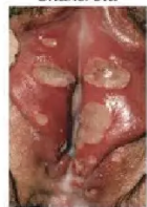

1. Borok karena Sifilis/ Ulkus Durum

Penyakit disebabkan oleh Treponema pallidum , keluhan luka di genital, anus ataupun rongga mulut.Biasanya dengan keluhan demam, lemah. Bagian luka berwarna merah, tidak nyeri, per mukaan bersih. Riwayat, berganti-ganti pasangan, berhubungan seksu al dengan penderita luka yang sama. Secara global, terdapat 10,6 juta kasus sifilis pada tahun 2008 dan terus terjadi pe ningkatan. Peningkatan terbesar pada usia 20-24 tahun dan 25-29 tahun, penularan sifilis meningkat pada laki lebih besar dari perempuan.

2. Ulkus Molle/ Chancroid

Penyakit infeksi pada alat kelamin yang akut, disebabkan oleh Haemophilus ducreyi. Gejala yang khas berupa ulkus nekrotik, nyeri pada luka, sering diserta nanah dan pembesaran kelen jar lipatan paha. Dasar boroknya kotor, bergaung,warna abu kekuningan, mudah berdarah, tepinya jelas. Tersebar di daerah tropic dan subtropic. Frekwensi pada perempuan lebih banyak. Penularan lewat kontak seksual. Pencegahannya menggunakan kondom Ketika melakukan seksual, tidak berganti pasangan.